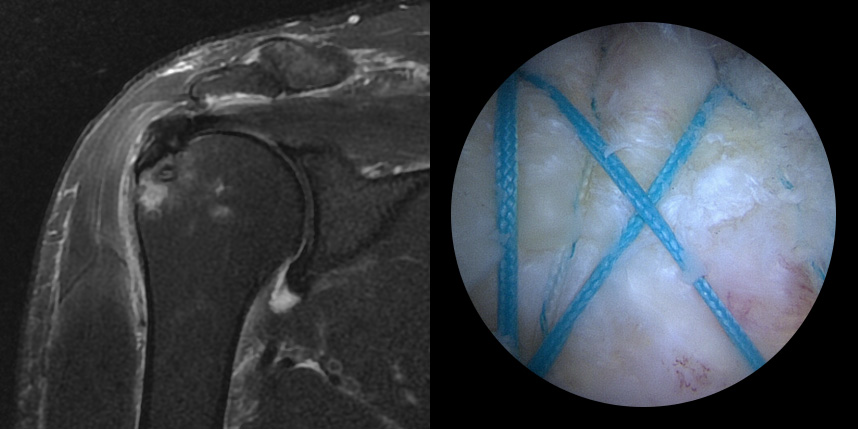

브릿지 봉합술

접촉면접과 힘줄

부착 압력이 높습니다.

초기,중기,말기 파열에

주로 사용됩니다.

상대적으로

재파열율이 낮습니다.